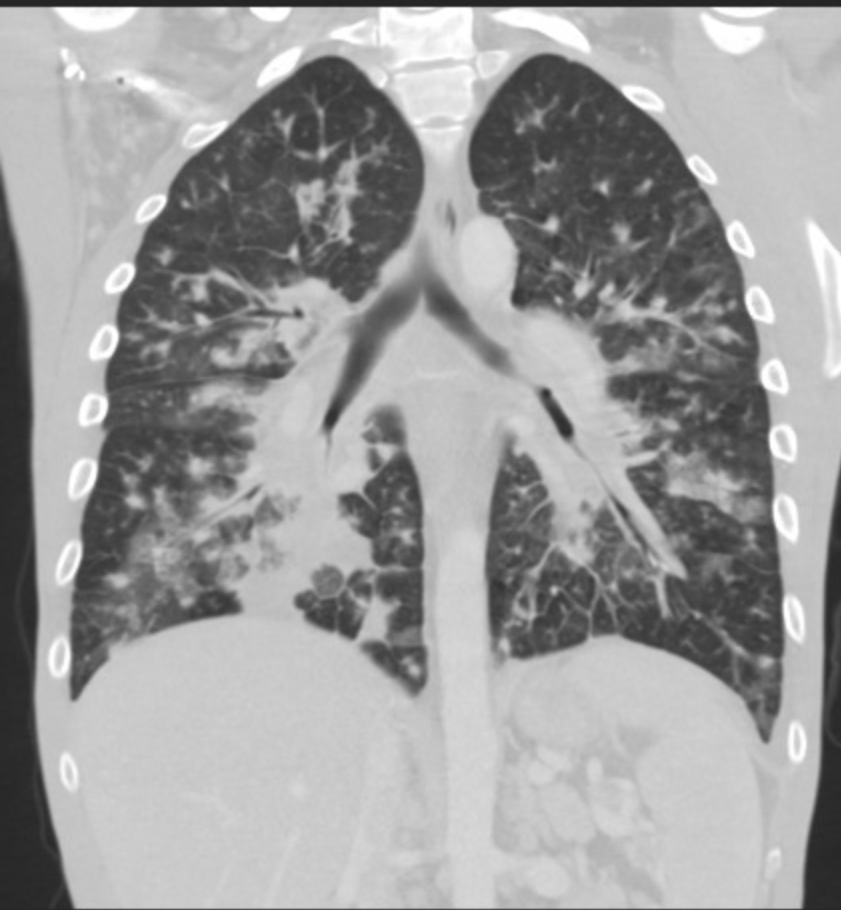

Gallery Lung Cancer Miscell KS cor 1a

KS cor 1a